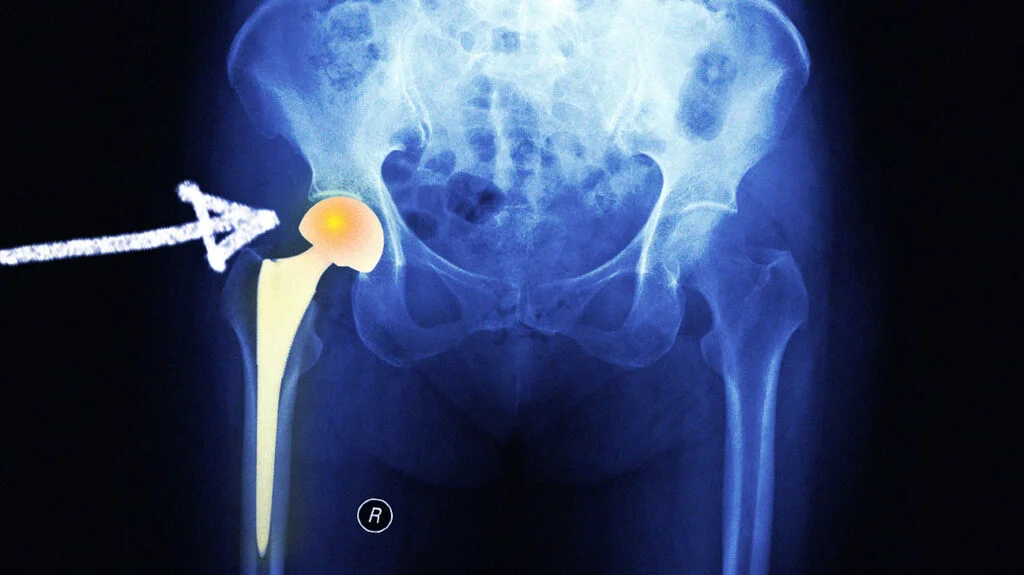

Hip arthoplasty

Hip arthroplasty is the surgical formulation or reformation of hip joint.

1) Cup or mold arthroplasty: In cup arthroplasty, the acetabulum and the head of femur are reamed down to an un traumatized surface and an appropriate size metal cup is fitted over the head of femur

2) Total hip arthroplasty: In total hip arthroplasty, the femoral head and neck, ream the femoral canal and insert a metal femoral component (which includes head neck and steam) into the femoral shaft.